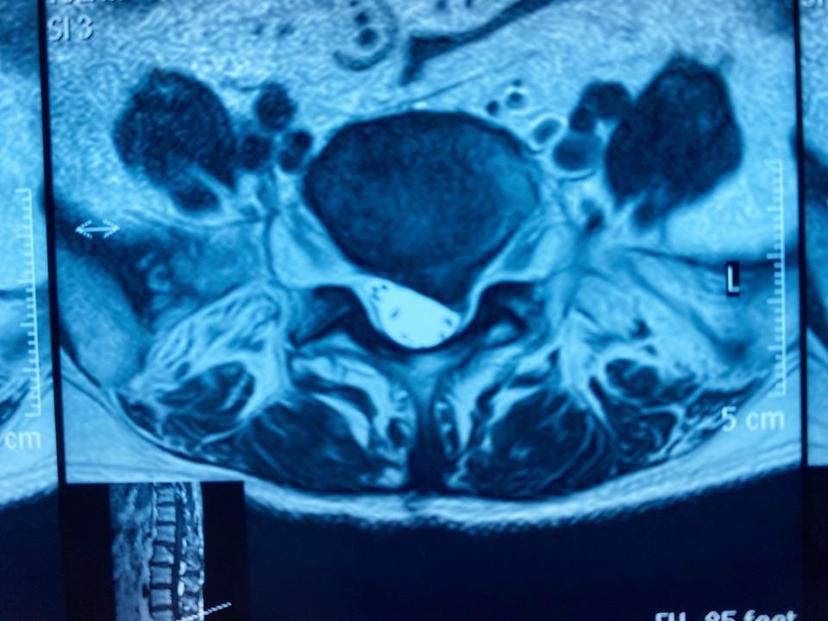

患者腰背痛10年,近半年左下肢疼痛麻木,不能正常行走,生活质量大大降低,经腰椎磁共振检查诊断出腰5-骶1椎间盘巨大突出,左侧神经受压明显,住院后当天采用局部麻醉下,经椎间孔镜技术微创治疗,整个手术过程仅仅半小时,切口0.5cm,完整取出压迫神经的髓核组织,后腰部及下肢不适症状完全消失,术后第二天早上出院,整个住院时间不到24小时!磁共振显示腰5-骶1椎间盘巨大突出,硬膜囊受压严重

磁共振平扫显示左侧神经根严重受压